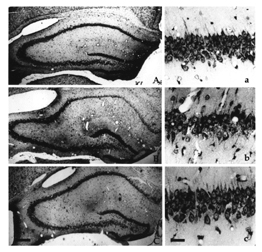

In the July 9 Proceedings of the National Academy of Sciences, the researchers demonstrated that EPO counteracts the nerve damage associated with two more common kinds of traumatic spinal cord injury in people. In rats with spines damaged by compression of the nerves, a single dose of EPO after injury boosted the animals’ hind leg movements within 12 hours of the injury compared with those of rats getting placebo injections. After 28 days, the EPO-treated rats–some of which were given additional doses on the second and third days after injury–had near-normal movement of their hind limbs, Cerami says, while animals given the dummy injections were still paralyzed.

The researchers also examined direct trauma to rats’ vertebrae and spinal cord that caused injuries and paralysis more severe than those resulting from compression. The researchers didn’t see any recovery of muscle movement or limb function in this group at first, whether or not the animals were given EPO. However, between the 4th and 12th day after injury, animals treated with one dose of EPO an hour after injury had better muscle tone and more coordinated leg movements and were also better at swimming than rats treated with a placebo were. When the researchers examined the rat spines 28 days later, the rats given EPO showed fewer signs of swelling and cell death surrounding the injury than placebo-treated rats did.